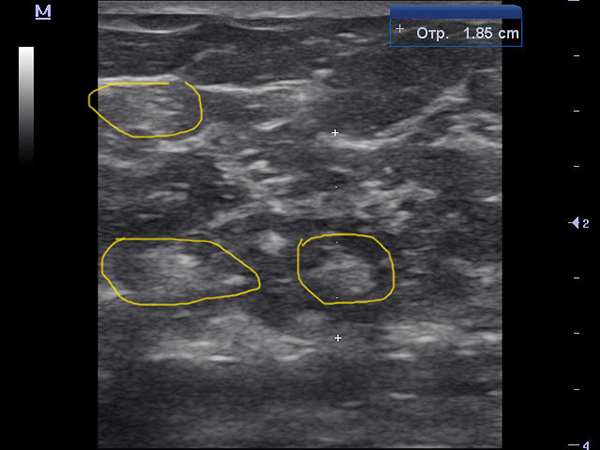

Это наверно В/Н квдрант.там обычно дольше остаются островки железистой ткани. Хотя она тут тоже по структуре с фиброзированием.

Правильно это верхне-наружный квадрант, но согласитесь железистой ткани много, фактически почти половина паеренхимы занимает жировая, а половину железистая ткань. Для женщины у которой 4 года климакс это много.

И мы в праве ей выставить железистую мастопатию!

В н/н квадранте:

В н/в частично как предпоследняя согорамма и частично как на последнем видео.

У женщины с менопаузой 4 года железистой ткани быть не должно, ну может только если отдельные очаги в наружном квадранте!

Эта картина характерна для раннего предменопаузального периода.

Но не как ни постменапаузального.

Вообщем женщине выставил заключение:

Диффузная железистая мастопатия, умеренно выраженная.

А клиника соответствующая заключению - умеренные боли в железах.